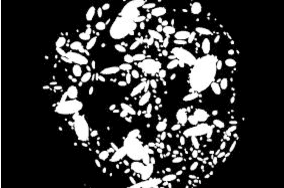

Abstract:This research aims to develop an efficient system for screening of diabetic retinopathy. Diabetic retinopathy is the major cause of blindness. Severity of diabetic retinopathy is recognized by some features, such as blood vessel area, exudates, haemorrhages and microaneurysms. To grade the disease the screening system must efficiently detect these features. In this paper we are proposing a simple and fast method for detection of diabetic retinopathy. We do pre-processing of grey-scale image and find all labelled connected components (blobs) in an image regardless of whether it is haemorrhages, exudates, vessels, optic disc or anything else. Then we apply some constraints such as compactness, area of blob, intensity and contrast for screening of candidate connectedcomponent responsible for diabetic retinopathy. We obtain our final results by doing some post processing. The results are compared with ground truths. Performance is measured by finding the recall (sensitivity). We took 10 images of dimension 500 * 752. The mean recall is 90.03%.